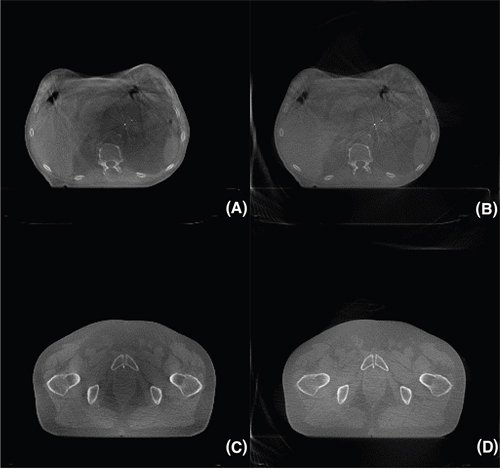

Figure 4: Reconstruction images of pancreatic (A), (B) and prostate (C), (D) cancer patient treated under radiation therapy. (A), (C) FDK, (B), (D) VS-SART-BB. A total of 655 x-ray projections were acquired in half-fan mode.